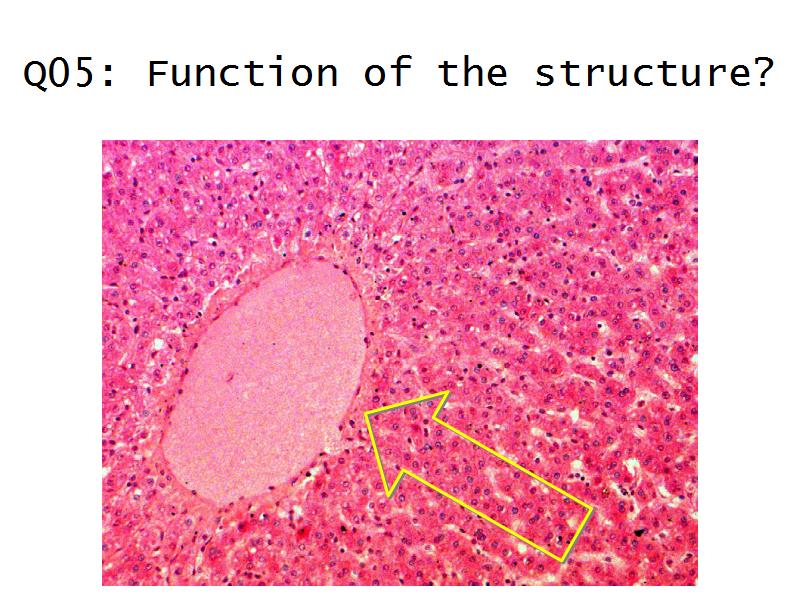

- The renal corpuscle

- Make an annotated diagram of a nephron, including the juxtaglomerular apparatus. Indicate the flow of blood and water in each part, and how solutes are filtered, secreted and reabsorbed.